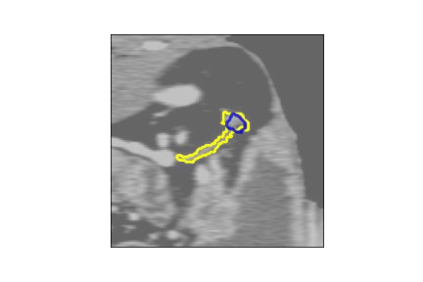

The human annotations are imperfect, especially when produced by junior practitioners. Multi-expert consensus is usually regarded as golden standard, while this annotation protocol is too expensive to implement in many real-world projects. In this study, we propose a method to refine human annotation, named Neural Annotation Refinement (NeAR). It is based on a learnable implicit function, which decodes a latent vector into represented shape. By integrating the appearance as an input of implicit functions, the appearance-aware NeAR fixes the annotation artefacts. Our method is demonstrated on the application of adrenal gland analysis. We first show that the NeAR can repair distorted golden standards on a public adrenal gland segmentation dataset. Besides, we develop a new Adrenal gLand ANalysis (ALAN) dataset with the proposed NeAR, where each case consists of a 3D shape of adrenal gland and its diagnosis label (normal vs. abnormal) assigned by experts. We show that models trained on the shapes repaired by the NeAR can diagnose adrenal glands better than the original ones. The ALAN dataset will be open-source, with 1,594 shapes for adrenal gland diagnosis, which serves as a new benchmark for medical shape analysis. Code and dataset are available at https://github.com/M3DV/NeAR.